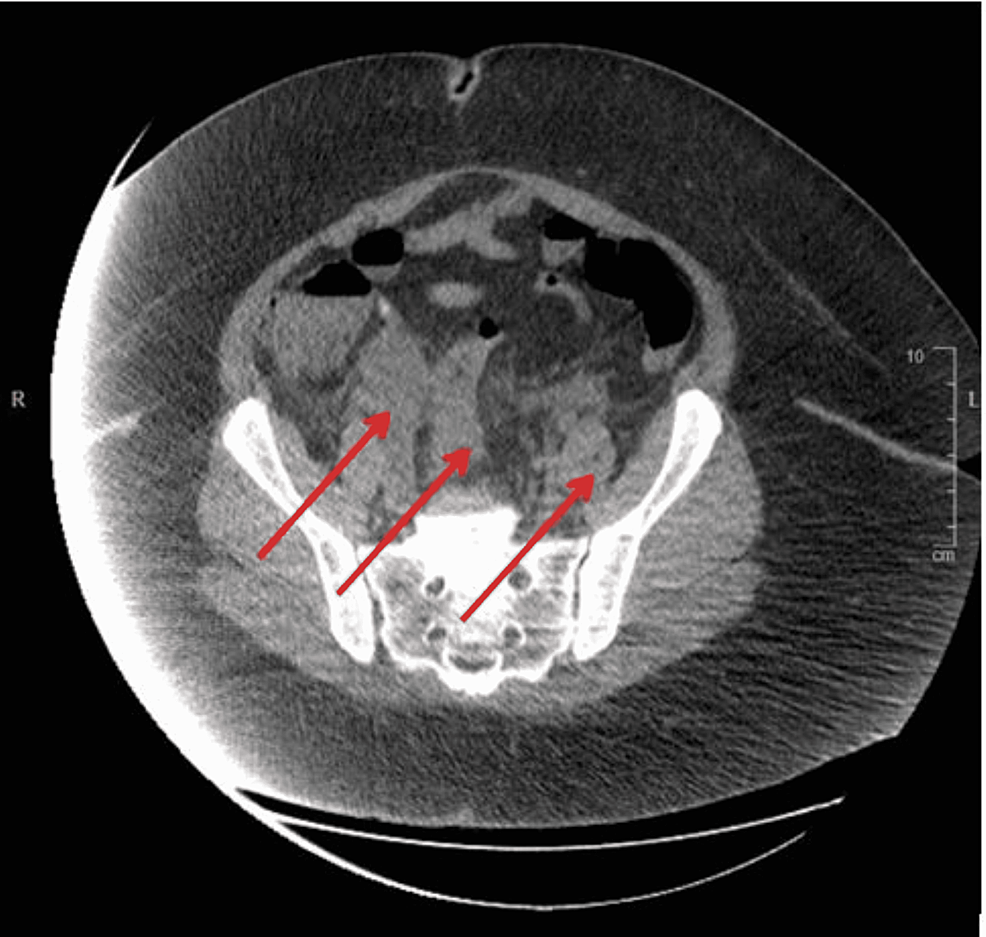

Cureus InteroExternal Hemorrhoids Complicated by IschioAnal Internal Hemorrhoids Medscape treatment with fiber is the primary conservative means to treat hemorrhoids, and preferred techniques for. Internal hemorrhoids do not have cutaneous innervation and can therefore be destroyed without anesthetic, and. As we age, and there are changes in the. acg strongly recommends symptomatic grade 1 and 2 internal hemorrhoids refractory to medical therapy. internal hemorrhoids are fibrovascular. Internal Hemorrhoids Medscape.